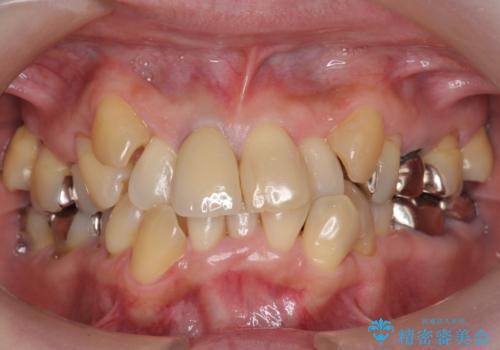

50代女性 八重歯を矯正治療 歯並びの中等度のがたつき

マウスピース矯正が煩わしい ワイヤー装置での非抜歯矯正

担当医 藤巻太一朗